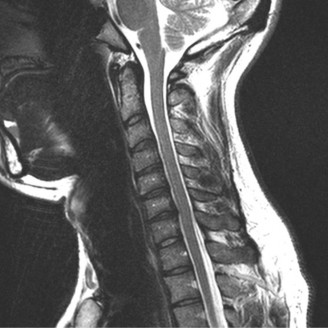

Magnetic Resonance Imaging and the Posterior Ligamentous Complex

To definitively assess the integrity of the soft tissue stabilizers and the neural elements, a Magnetic Resonance Imaging (MRI) scan without contrast was performed. Historically, textbooks propagated the "50-50-25 rule," suggesting that a burst fracture was inherently unstable if it exhibited >50% canal compromise, >50% loss of vertebral body height, or >25 degrees of kyphosis. Modern spine trauma surgery has largely debunked this rigid radiographic dogma. We now understand that these bony metrics alone do not dictate mechanical instability. The true arbiter of stability is the Posterior Ligamentous Complex (PLC).

The MRI, particularly the Short Tau Inversion Recovery (STIR) and T2-weighted sagittal sequences, provided the definitive diagnosis. The images demonstrated profound hyperintensity and discontinuity of the ligamentum flavum, the interspinous ligaments, and the supraspinous ligaments at the T12-L1 level. The facet joint capsules were also disrupted, indicated by fluid within the joints. This complete failure of the PLC means the posterior tension band is gone. Regardless of the bony parameters, this spine cannot resist physiological flexion loads. If treated non-operatively, this injury will inevitably lead to progressive kyphosis, delayed neurological deficit, and intractable pain.